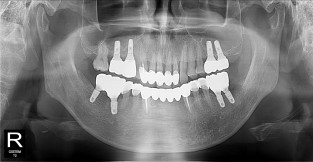

• 11

하악

치료기간 : 2021-11-30 ~ 2022-07-13

1. 상기 x-ray 이미지 모두 동일한 해당 의료기관에서 진료한 환자입니다.

2. 상기 x-ray 이미지 모두 동일 인물의 것입니다.

3. 치료 전 이미지는 2021-11-30에 촬영했으며, 치료 후 이미지는 2022-07-13에 촬영하였습니다.

4. 상기 x-ray 이미지 모두 동일 조건에서 환자분의 동의를 받아촬영되었습니다.

* 임플란트 시술은 환자분의 상태(고혈압, 당뇨 등)에 따라 부작용이 있을 수 있으니, 반드시 전문의와 상담이 필요합니다.

* 임플란트 수술 부작용

: 수술 후 출혈, 교합, 통증, 붓기, 염증 등의 문제점이 발생할 수 있습니다.)